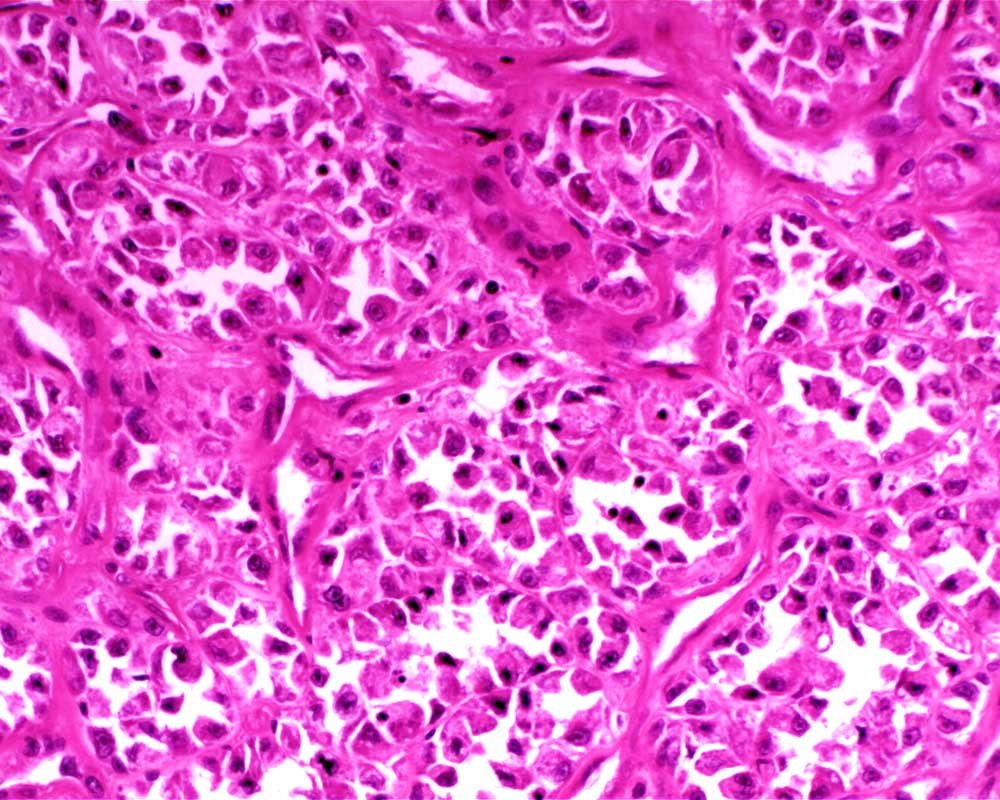

Case: ThighMass

Final Diagnosis: